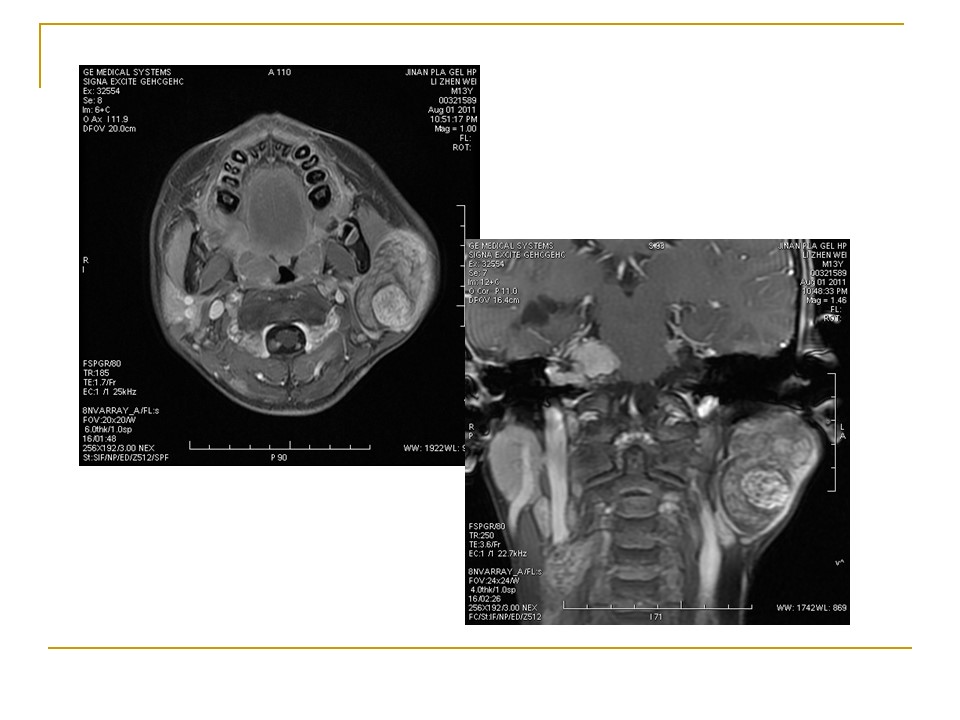

腮腺混合瘤MRI表现